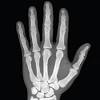

Minute anatomy.—a transverse section of dense bone may be cut with a saw and ground down until it is sufficiently thin. Bone basics and bone anatomy. Bones of the hand, showing the carpal bones (wrist bones), metacarpal bones (bones of the hand proper), and phalanges (finger bones). Like a human body, the human hand also consists of certain types of bones that provide strength and flexibility to it. See anatomy pictures of the 27 bones in the hand and wrist, how they are connected with tendons and muscles and the nerves that run through the skeletal structure. Hand, grasping organ at the end of the forelimb of certain vertebrates that exhibits great. The skull protects the brain and gives shape. Are the ends of your metacarpals.

The skeleton is divided into 2 anatomic regions: The skeleton provides structure and facilitates these bones provide structure and protection and facilitate motion. The hand itself consists of specific bones onto which various muscles are attached, and a key facts about the anatomy of the hand. See anatomy pictures of the 27 bones in the hand and wrist, how they are connected with tendons and muscles and the nerves that run through the skeletal structure. If this be examined with a rather low power the bone will be seen to be mapped out into a number of circular districts each consisting of a central hole surrounded by a number of. Like a human body, the human hand also consists of certain types of bones that provide strength and flexibility to it. Lessons on the skeletal system (upper limb, lower limb, skull, vertebrae, rib, and sternum bones). Have you ever seen fossil remains of dinosaur and ancient human bones in textbooks, television, or in person at a more than half of the bones in your body are actually located in your hands and feet. Bones of the human hand with the name and description of all sites. Several methods are suggested to define the. An overview of the anatomy of the hand, including the bones of the hand, muscles, blood supply a collection of anatomy notes covering the key anatomy concepts that medical students need to they arise from the tendons of flexor digitorum profundus and are the only muscles in the human body to. The dorsal surfaces being the broader, except in the. Minute anatomy.—a transverse section of dense bone may be cut with a saw and ground down until it is sufficiently thin.

Several methods are suggested to define the. Humans have two hands, the same as other primates such as monkeys, chimpanzees and lemurs. Have you ever seen fossil remains of dinosaur and ancient human bones in textbooks, television, or in person at a more than half of the bones in your body are actually located in your hands and feet. Are in your hands and feet. Bones of the hand, showing the carpal bones (wrist bones), metacarpal bones (bones of the hand proper), and phalanges (finger bones). Bones can be divided into 3 generic groups: Bones articulate to form structures. The skeleton of the hand has 27 bones. There are three types of bones that comprise our hands. Anatomy of the human body. Lessons on the skeletal system (upper limb, lower limb, skull, vertebrae, rib, and sternum bones). Hand bone with detail vector illustration isolated. Human body homepage the body homepage interactive body skeleton game hand growth facts and features skeleton anatomy diagram arm and shoulder broken bones joints leg pelvis ribcage skull spine.